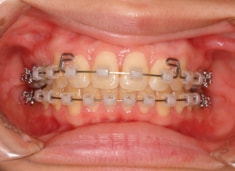

治療法:表の矯正(T21ブラケット)

治療開始時